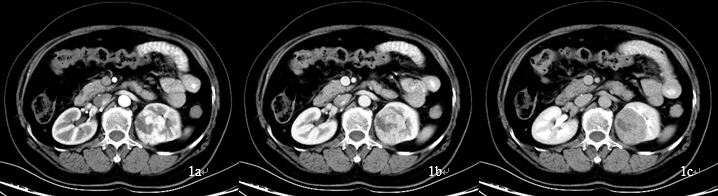

病例资料 患者女性,58岁,既往体健,查体发现左肾占位,行泌尿系CTU扫描,左肾占位呈典型 “快进快出”强化方式(图1),考虑肾癌、透明细胞癌可能性大。左肾上腺见结节灶,呈明显均匀强化(图2),肾上腺转移瘤待排,行能谱CT检查。

CT图像 图1:左肾占位,增强扫描皮质期不均匀明显强化,实质期持续强化,延迟期造影剂退出呈低密度,为典型肾癌的CT表现。